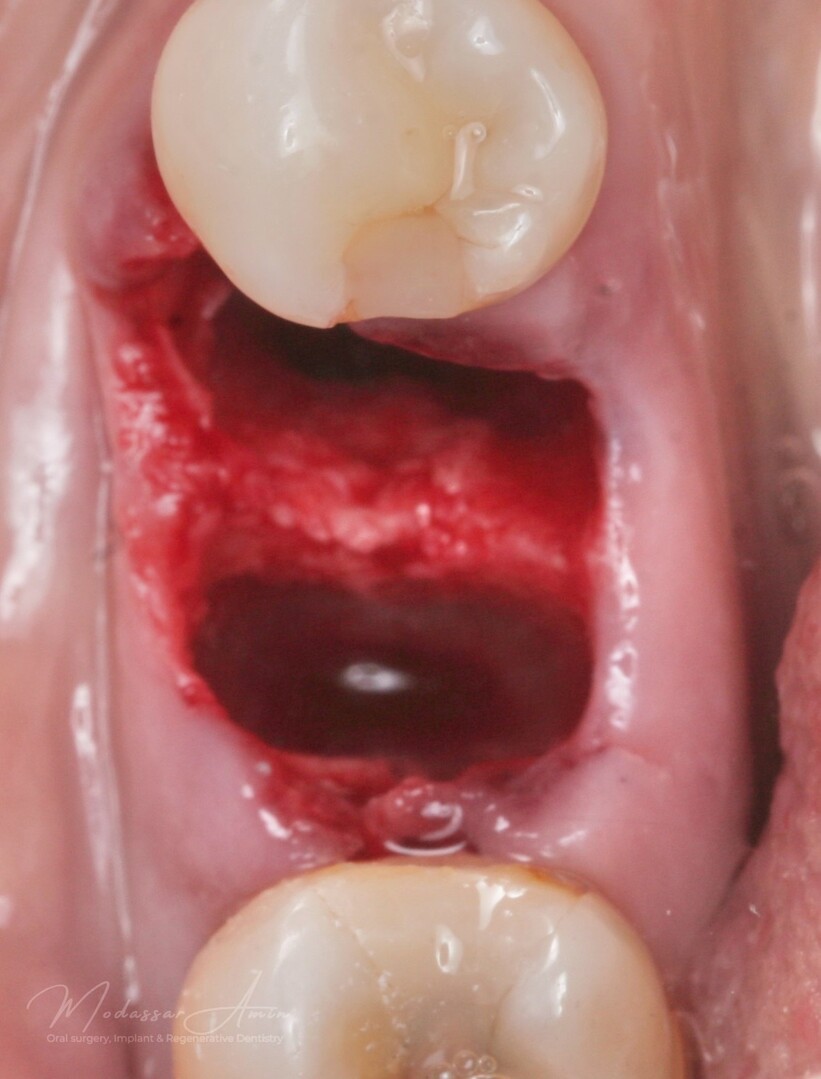

PATIENTFALL

"Pasienten presenterte med tann 46 som ikke kunne bevares grunnet en dyptgående infraksjon inn i furkasjonen. Forholdene lå til rette for en immediate implantatbehandling. Ved hjelp av Versah osseodensifikasjonsbor ble det interradikulære beinet ekspandert på en skånsom og forutsigbar måte, noe som ga høy primærstabilitet (>40 Ncm) til tross for en lokal bendefekt apikalt mesialt etter kronisk apikal periodontitt. Den gode stabiliteten muliggjorde bruk av SSA (Sealing Socket Abutment) for forsegling. På grunn av tynn bløtvevsfenotype bukkalt ble behandlingen supplert med bindevevstransplantat (CTG)"

Initial

Minimalinvasiv extraktion